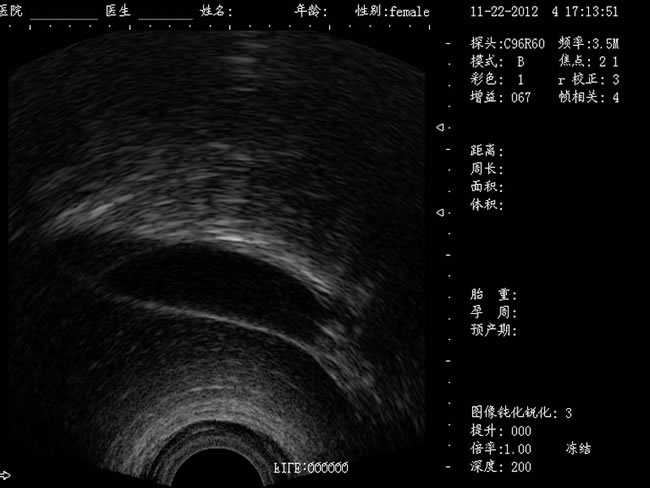

超聲婦產科手術監視儀-可視人流機

DW-CE780推車式全數字彩色多普勒超聲診斷儀

DW-400

定位精確 手術效率高:實時動態頻率掃描等全數字超聲成像技術、生成精確的圖像引導手術器械迅速到大手術位置,避免損傷子宮內膜和子宮穿孔的現象,即減輕了患者的痛苦又極大提高了手術效率。

CXA10R/6.5MHz 腔內探頭

選配:CXA60R/3.5MHz 凸陣探頭

隨著醫療技術水平的提高,目前婦產科手術中所應用的相關設備也有了加大的改進。尤其是在人工流產手術中,將B超婦產科手術監視儀應用到手術過程中,彌補傳統手術中所采用設備的不足之處,減輕手術中患者的疼痛感覺,使得手術順利的完成。這種儀器相比于傳統的儀器來說,其在操作上更為方便和簡單,能夠對妊娠反應有很好的療效。